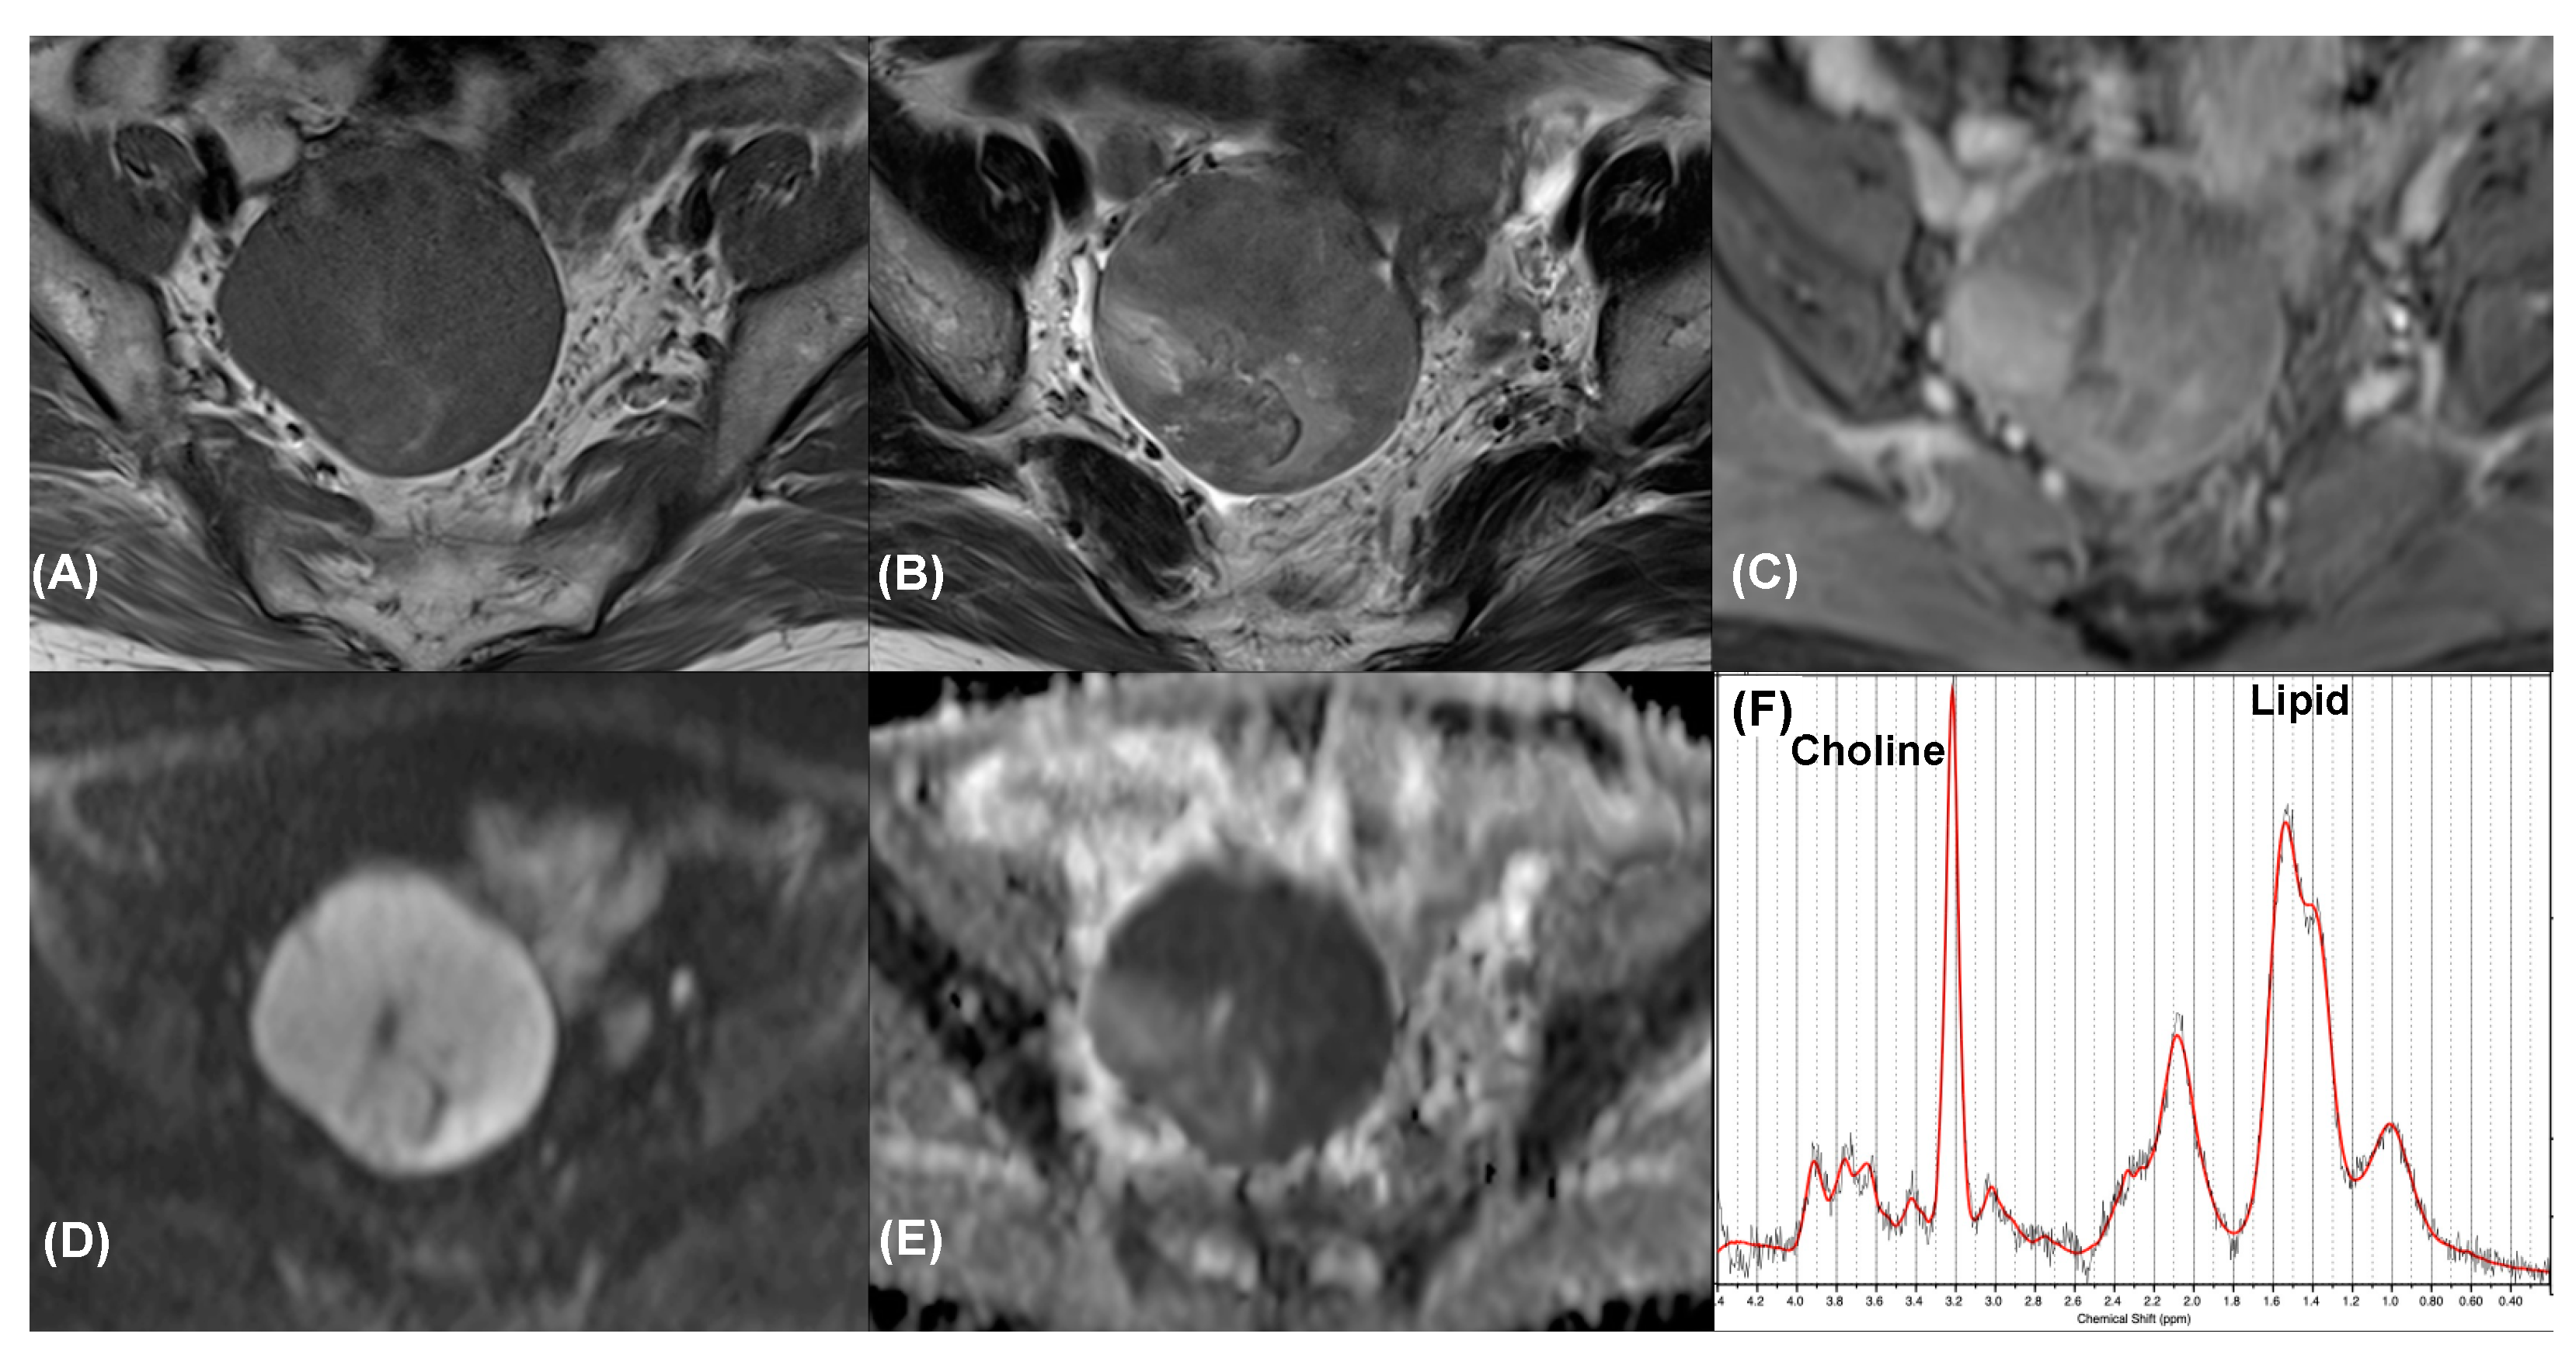

| 4 | Clear cell carcinoma | Yes | 5 | FN | TP * |

| 5 | Clear cell carcinoma | Yes | 4 | FN | TP * |

| 6 | Clear cell carcinoma | Yes | 4 | FN | TP * |

| 7 | Endometrioid carcinoma | Yes | 4 | FN | TP * |